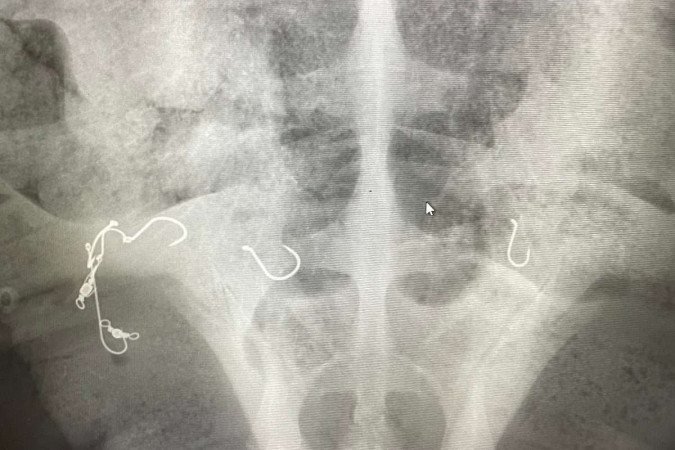

Os raios-x fizeram a revelação de sete ganchos no animal -  (crédito: Reprodução/ Facebook/ Taronga Zoo Sydney)

Os raios-x fizeram a revelação de sete ganchos no animal. A tartaruga ainda segue em recuperação, o animal se alimenta e nada na piscina de reabilitação do hospital. A equipe segue na expectativa para a recuperação, mesmo que isso seja um longo caminho.